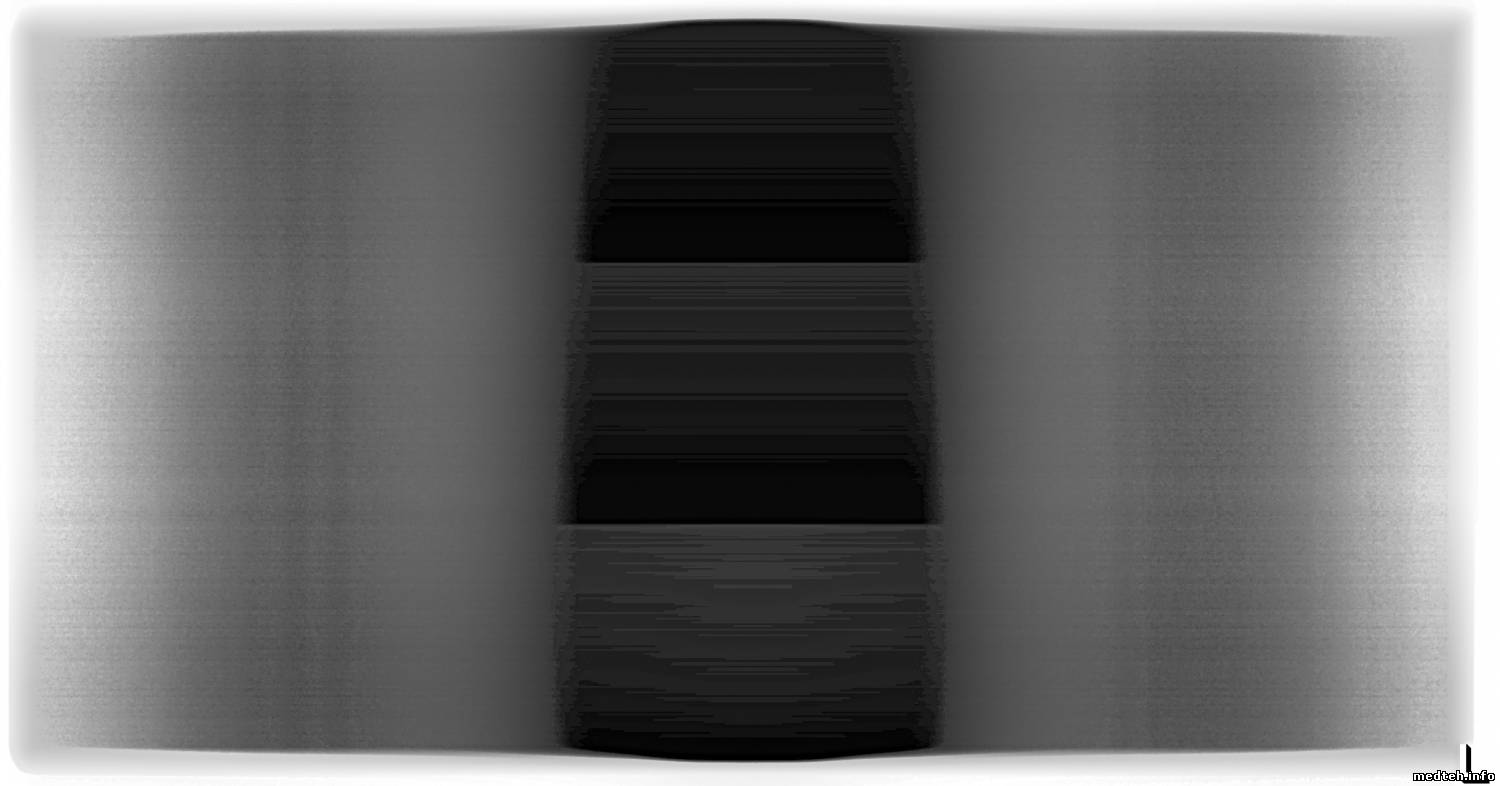

Геометрические искажения, там калибруються тоже программно, а вот горизонтальные полосы на снимке, ума не приложу, как убрать. Несколько снимков во вложении. На середине снимка хорошо видно 3-и приёмника (детектора). Чем дальше,тем хуже. Чётче видны горизонтальные полосы.